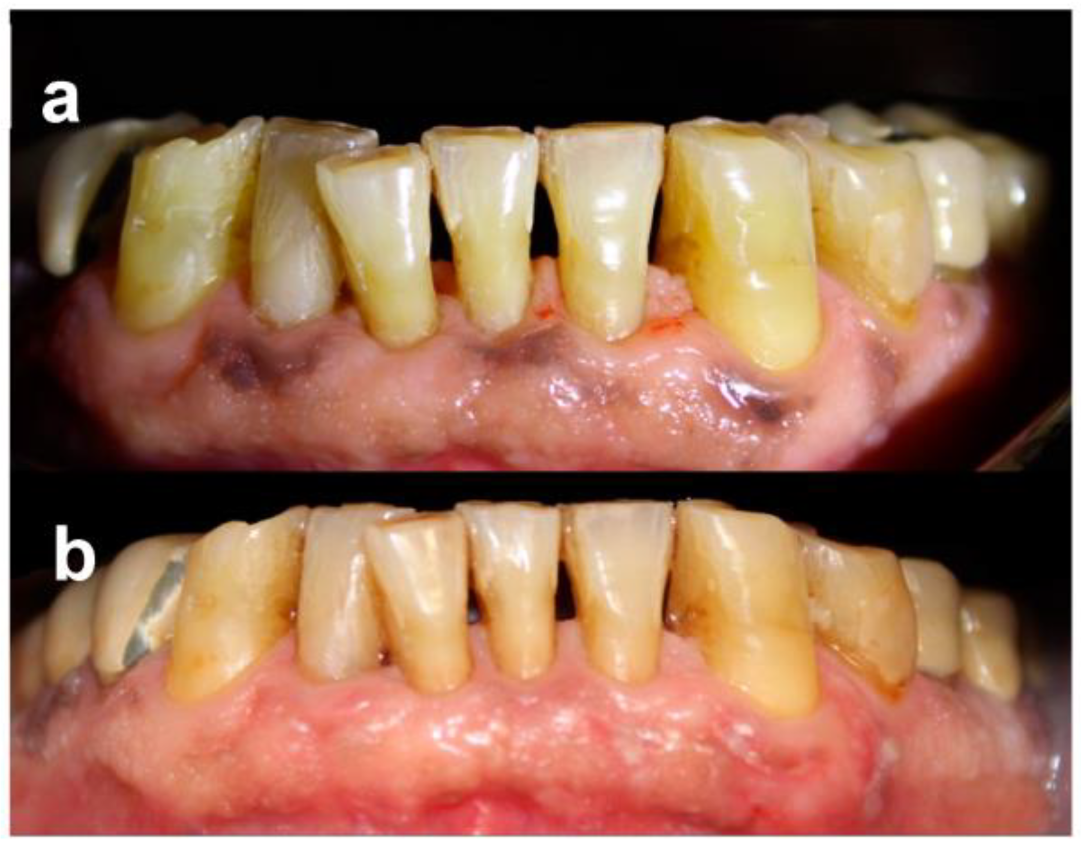

- Score 0: no clinical pigmentation (pink-colored gingiva);

- Score 1: mild clinical pigmentation (mild light brown color);

- Score 2: moderate clinical pigmentation (medium brown or mixed pink and brown);

- Score 3: heavy clinical pigmentation (deep brown or bluish-black color).

- Score 0: no pigmentation;

- Score 1: solitary unit(s) of pigmentation in the papillary gingiva without extension between neighboring solitary units;

- Score 2: formation of continuous ribbon extending from neighboring solitary units.